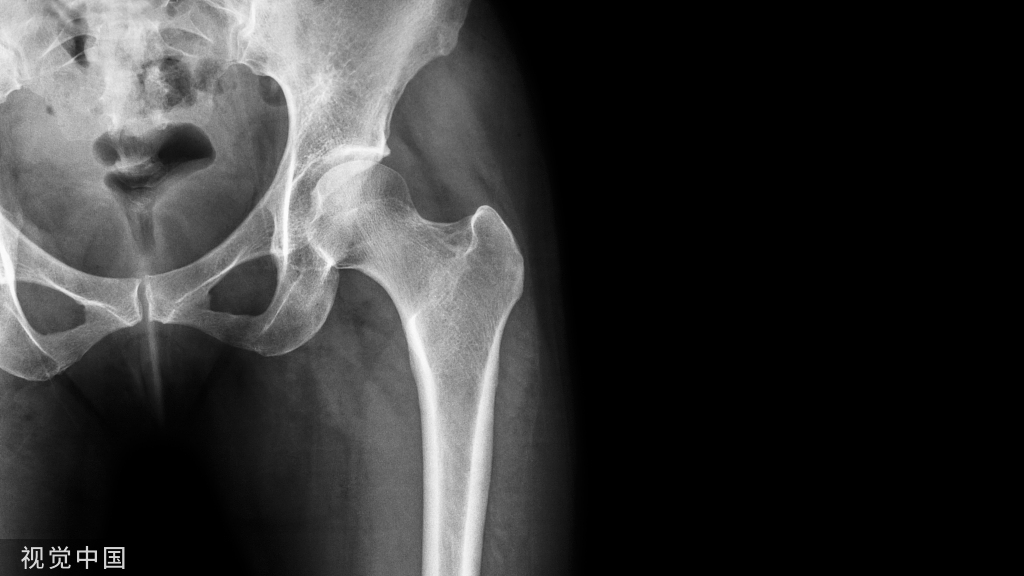

(四)、髋部手术的体位(全髋、半髋置换) 侧卧位

- 患者健侧卧位,头偏向一侧置头圈。

- 腋下垫一腋垫,双上肢用束臂带固定于双层搁手架上。

- 在耻骨联合和骶尾部用体位固定架固定,在体位固定架和身体间加一软垫保护。

- 健侧下肢弯曲,在膝关节处及踝关节处垫一脾垫,大腿上放一海绵垫约束带固定。